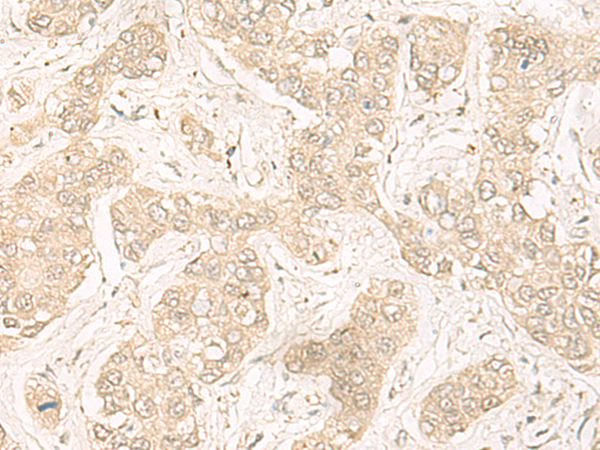

IHC positive control: |

Human liver cancer |

IHC Recommend dilution: |

30-150 |